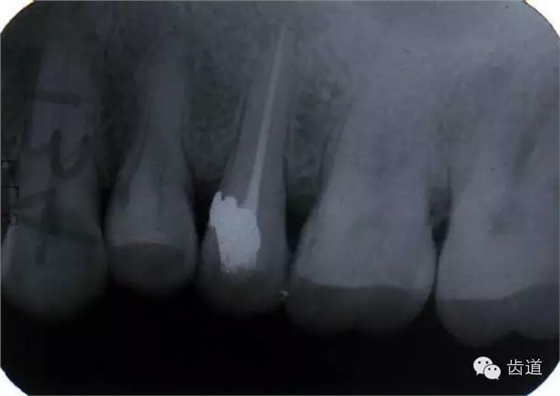

左上5牙頸部側(cè)穿